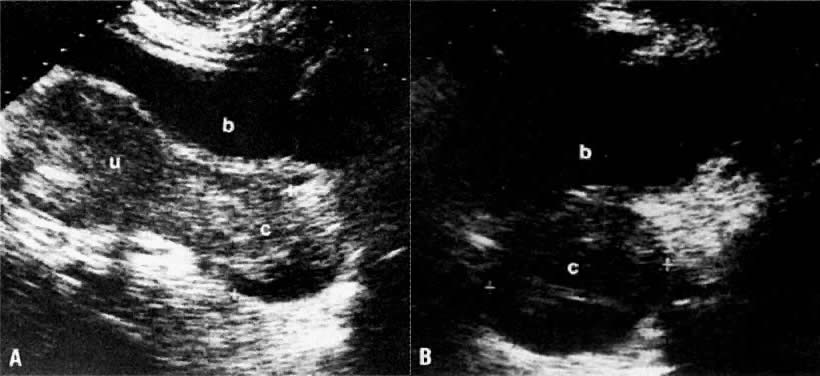

Ultrasound may play a significant role in local staging. The size of the uterus, which can be accurately evaluated by ultrasound, is not helpful in staging endometrial carcinoma. There is, however, a statistically significant difference in the echo pattern and shape of the uterus between stages I and II and stages III and IV. Of patients with tumor stages I and II, 94% had a normal or bulbous uterus and a normal or decreased echo pattern; however, of patients with tumor stages III and IV, 80% had a lobular and/or mixed-echo pattern.47 On TVUS, stage IA disease is diagnosed when there is no disruption of the normal hypoechoic halo that surrounds the hyperechoic endometrial stripe (see Fig. 21A). Muscular invasion (stage IB and IC) is indicated by the lack of uniformity of this halo (Fig. 25). The degree of invasion is evaluated by comparing the depth of the endometrium to the depth of the myometrium. Using these criteria, Cagnazzo and associates70 found TVUS to be 78% accurate in assessing myometrial invasion, with a sensitivity of 80%, specificity of 77%, positive predictive value of 87%, and negative predictive value of 66%. Similar values for MRI in the same study were 83%, 87%, 78%, 82%, and 84%, respectively.70 Others have also found no difference in the staging accuracy of TVUS and T2-weighted MRI (68% vs 68% to 74%).68,71 In another study, TVUS was found to be accurate for detecting both myometrial invasion and cervical extension.72 Errors of depth overestimation of myometrial invasion by ultrasound can occur when the tumor has a significant intraluminal component, atrophic myometrium, associated fibroids, pyometra, and poor tumor/myometrial contrast.68,73 Errors of underestimation resulted predominantly from microscopic invasion. Gross cervical involvement by endometrial carcinoma causes enlargement of the cervix, which can also be accurately assessed by ultrasound (Fig. 26).

Fig. 25. Stage IC endometrial carcinoma. Sagittal TVUS image of the uterus shows marked, inhomogeneous endometrial thickening ( thick arrows ). Note the deep invasion of the anterior myometrium ( thin arrow ). ( b, bladder.)

Fig. 26. Stage II endometrial carcinoma with cervical invasion. A. Sagittal sonogram of the uterus and cervix. B. Transverse sonogram of the cervix. Note the inhomogeneous endometrial thickening and the cervical enlargement caused by invasion of the endometrial carcinoma. ( u, uterus; c, cervix; b, bladder.)